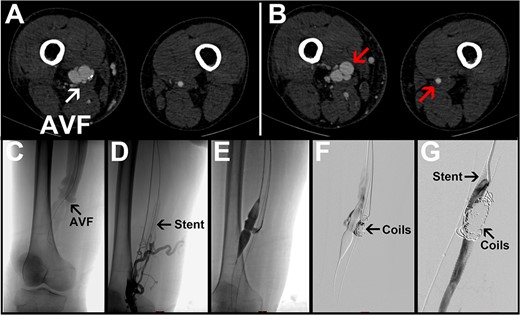

A 75-year-old male patient complained of having had bilateral lower limb edema for 1 month. The physical examination revealed sunken edema of both lower limbs, worse on the right side, with a tremor on the right medial thigh. The patient had a previous history of underlying diseases including heart failure, atherosclerosis, hypertension, emphysema, and an NYHA classification of 4 for cardiac function. On admission, a computed tomography angiography (CTA) examination showed a heterogeneous thickening of the lumen of the right femoral artery compared with the left. The right femoral artery was ~14.17 mm in diameter proximally and 5.32 mm in diameter distally; the right femoral abnormal fistula was ~17.28 mm in diameter proximally and 21.01 mm in diameter distally of the femoral fistula. There was a fistula of ~10.25 mm in diameter between the arterioles (Fig. 1A and B). The diagnosis was an AVF. Decades ago, the right inner thigh was struck by a heavy object at work. At that time, there was localized edema, bruising and pain in the inner thigh. Ultrasound and X-ray imaging were performed at the hospital, and there were no abnormalities in the blood vessels and femur. It was not taken seriously attention, and the symptoms were relieved after 2 weeks of rest. There was no history of other trauma. We therefore think that he had an AVF caused by trauma. The patient’s laboratory parameters, computed tomography, and electrocardiogram results were suggestive of abnormal cardiac and pulmonary function. The key to treatment was to improve the circulatory compromise caused by the AVF while maintaining the patient’s basic vital signs. We have developed a variety of treatment options for our patients. Endovascular treatment has less impact on the patient’s circulatory function. However, the patient had atherosclerosis and was prone to embolisms. If the endovascular treatment failed, a surgical repair would be the only remaining option. Through repeated communication with the patient and his family, weighing the pros and cons, the patient opted for endovascular treatment. Under local anesthesia, we introduced a guidewire via the right femoral artery route through the fistula, and one 8 mm × 10 cm Fluency™ stent (BD, Franklin Lakes, NJ) was introduced via the guidewire to be released in the distal segment of the femoral artery. A 16 mm balloon was introduced via the right femoral vein to seal the fistula. The proximal femoral artery was angiographic, and the abnormal tract was not completely closed due to the large diameter of the femoral artery and the continued high-velocity contrast flow that was still present. We then introduced another catheter through the right femoral artery and filled the dilated area of the right femoral artery with 10 and 12 mm coils. The final angiogram showed the satisfactory deployment of the stent and correct exclusion of the fistula tract from both the arterial and venous sides (Fig. 1C–G). Postoperatively, the patient’s cardiopulmonary function did not worsen compared with the preoperative period, the abnormal tremor in the inner thigh disappeared, and the edema of the lower extremity was obviously eliminated. The patient was discharged with instructions to continue long-term treatment with clopidogrel and acetylsalicylic acid. At the 6-month follow-up, the patient complained of gastric discomfort and mild edema in the lower limbs again. The heart failure symptoms were resolved.

Representative images for Case 1. (A) Preoperative CTA image with the arrow pointing to an arteriovenous fistula. (B) The left arrow points to the obviously dilated right femoral artery; the right arrow points to the normal left femoral artery. (C–G) Intraoperative angiogram images. R, right side; L, left side; AVF, arteriovenous fistula.